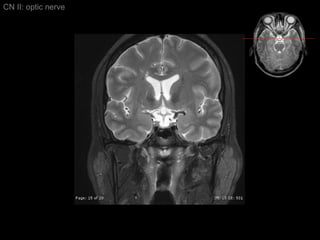

CN II: optic nerve Axial T2/ inferior to superior

CN II: optic nerve